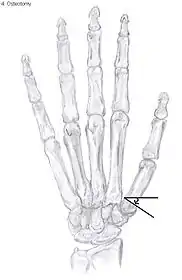

Metacarpal osteotomy

The aim of metacarpal osteotomy is to change the pressure distribution on the TMC joint. The hope is that this will slow the pace of development of osteoarthritis. There is no evidence that this procedure can modify the natural course of TMC OA. Osteotomy may be considered for people with mild arthritis.[24]

During osteotomy, the metacarpal is cut and a wedge shape bone fragment is removed to move the bone away from the hand.[36] Postoperative, the thumb of the patient is immobilized using a thumb-cast.

Possible complications are non-union of the bone, persistent pain related to unrecognized CMC or pantrapezial disease and radial sensory nerve injury.[24]